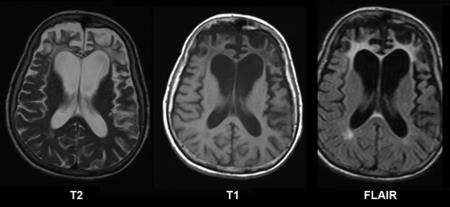

ALS診断のための検査:MRI

ALSでは通常MRIでは異常所見は見られないが、他疾患の鑑別が主な役割。

時にFLARIRやT2強調画像で、皮質脊髄路にそって高信号が認められることがある。

内包後脚および大脳脚に淡いT2高信号が認められる。

大脳脚レベル以下や中心前回皮質下まで続く高信号はALSの病的変化と考えられる。

T2強調像や磁化率強調像で中心前回皮質の信号がみられる頻度が高い。